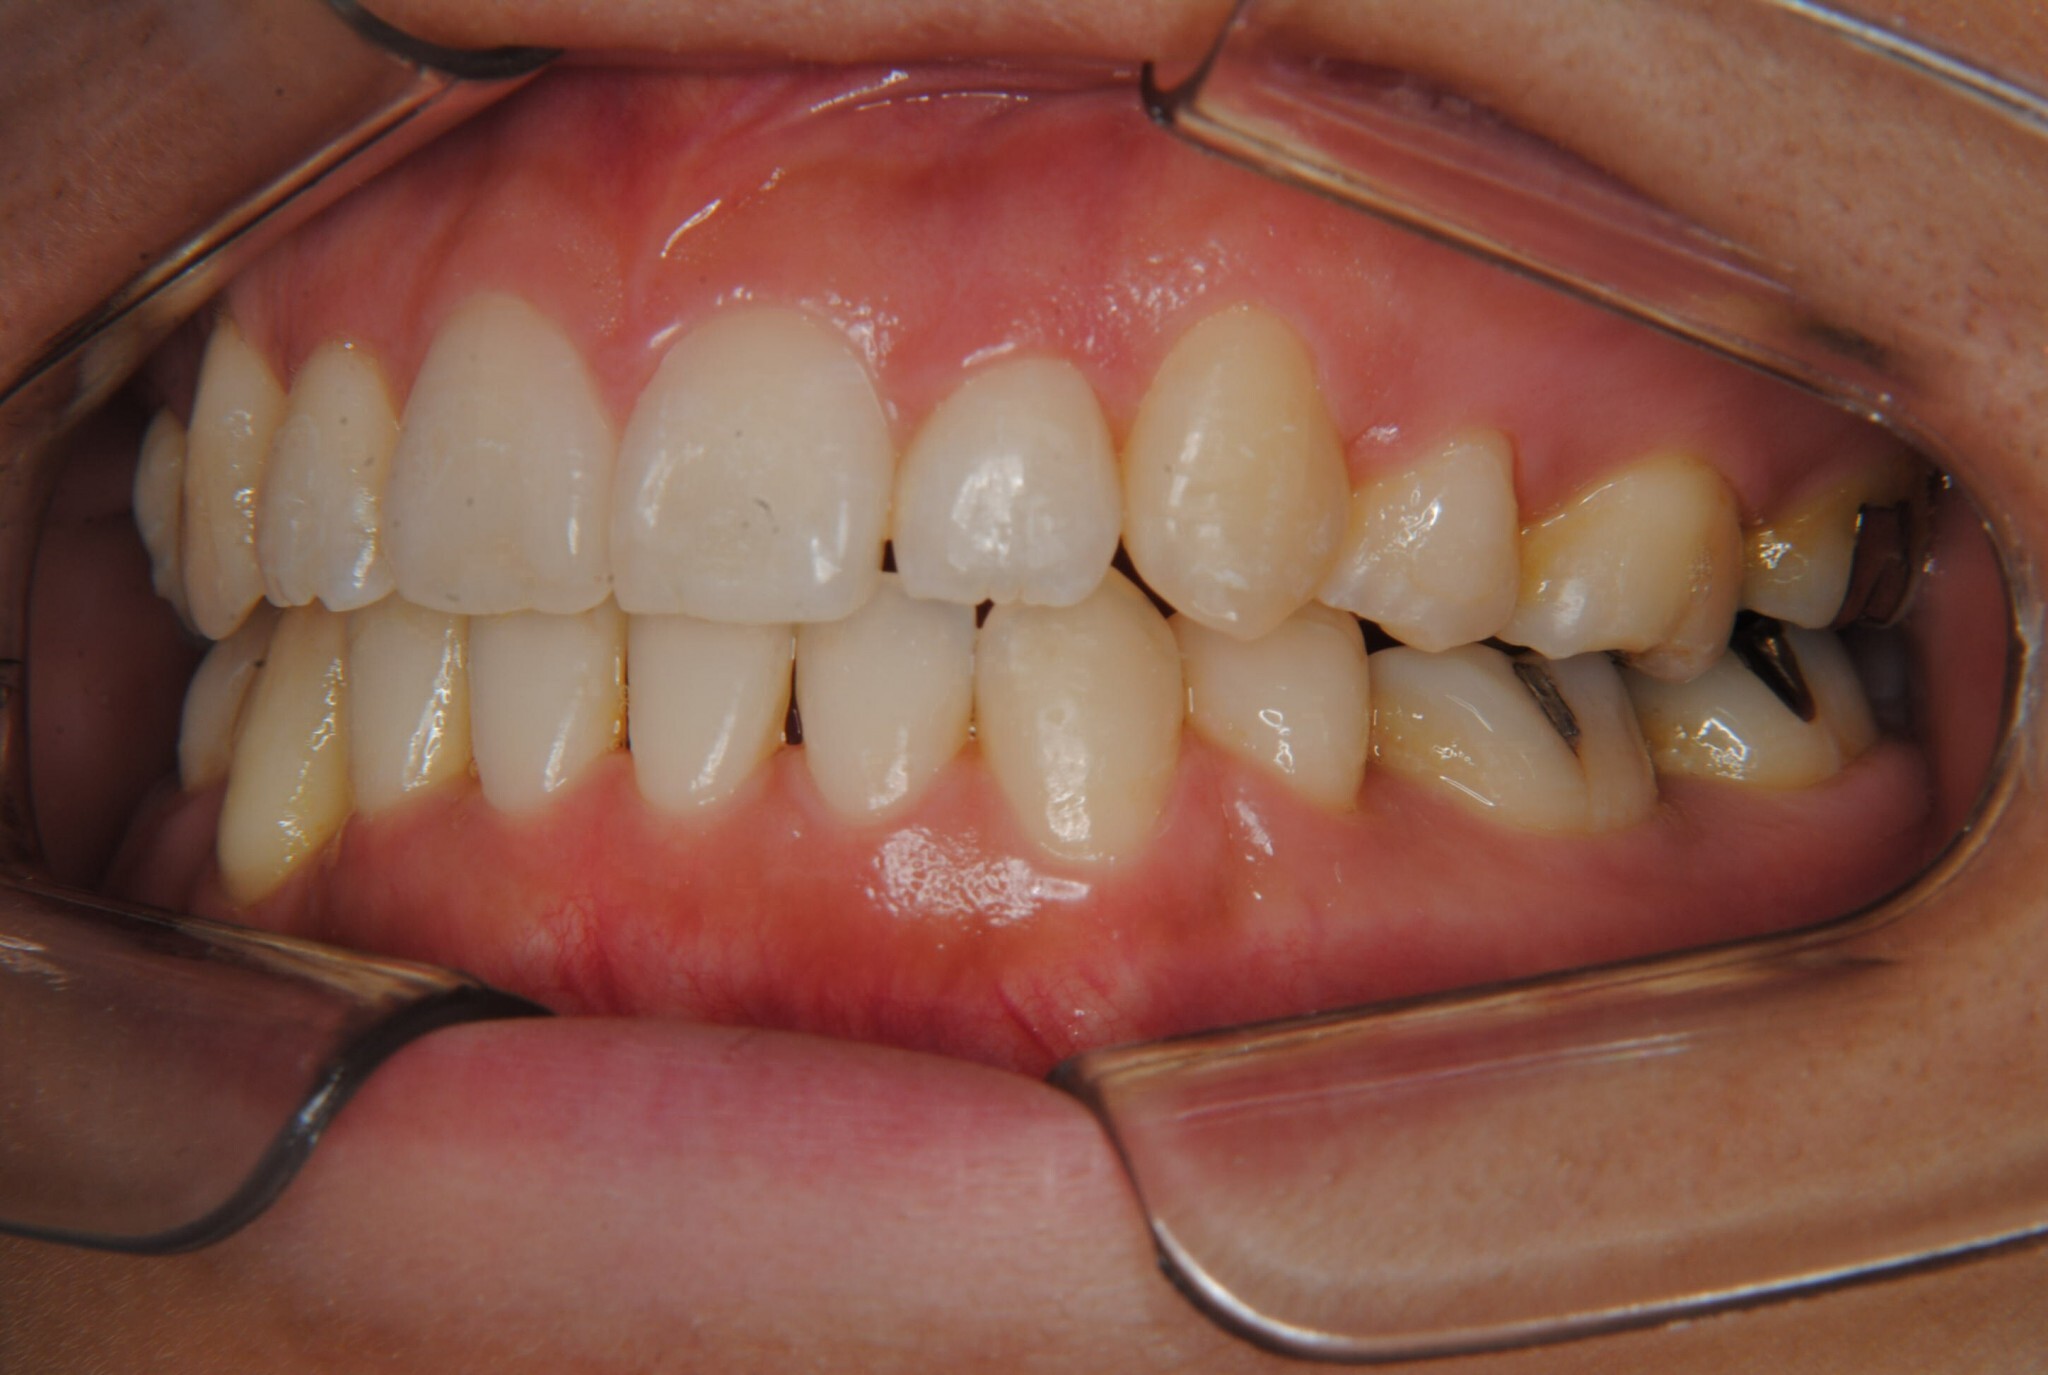

①主訴:八重歯、前歯のガタガタ、真ん中の不一致を治したい

②診断名:AngleⅠ級叢生

④治療に用いた主な装置:マルチブラケット装置(T21ブラケット)

⑤抜歯部位:上下左右第一小臼歯

⑥治療期間:1年7ヶ月